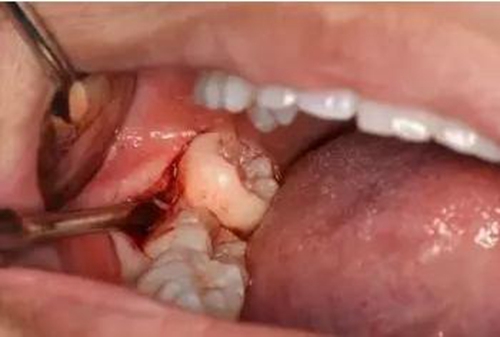

圖11.以頰側(cè)骨板做支點(diǎn)、往上脫位

圖12. 近中、頰側(cè)兩個(gè)部位用挺使48牙冠完全脫位

圖13.清理牙槽窩、對位傷口

圖14.僅在遠(yuǎn)中縫合兩針,不宜太緊。